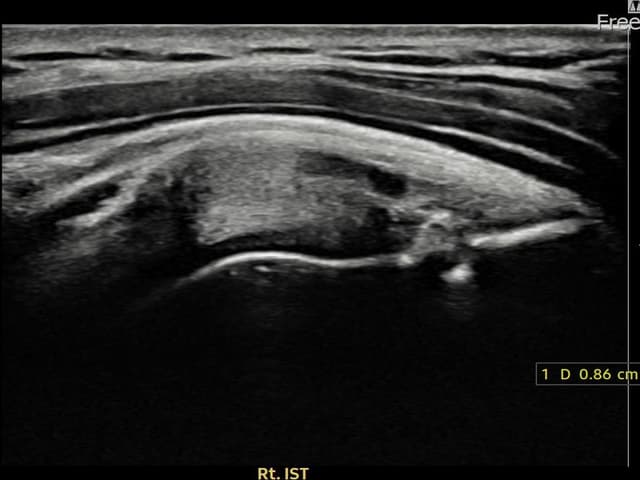

[経過期間: 23.12.14~24.02.22]

[縫縮術] 超音波検査にて右 棘下筋腱 付着部部分断裂(8.6mm × 4mm (腱厚の約45%欠損))を確認。縫縮術施行後、腱の連続性が回復し、日常生活に復帰されました。